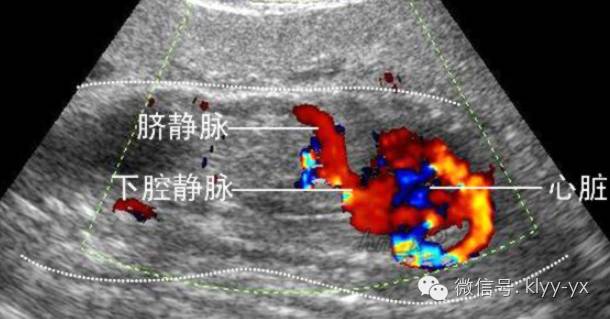

彩超并非是字面意义上的“彩色的B超”,而是在普通B超的基础上出现了彩色-多普勒超声波探测诊断技术,会用彩色标注心脏、血流等指标,彩超观测到的图像以红蓝两色为主。

这种技术能够观测到胎儿的血液流动情况,有利于及时发现胎儿的异常。例如:胎儿颈部如有血流环,则意味着发生了可导致窒息死亡的脐带绕颈。